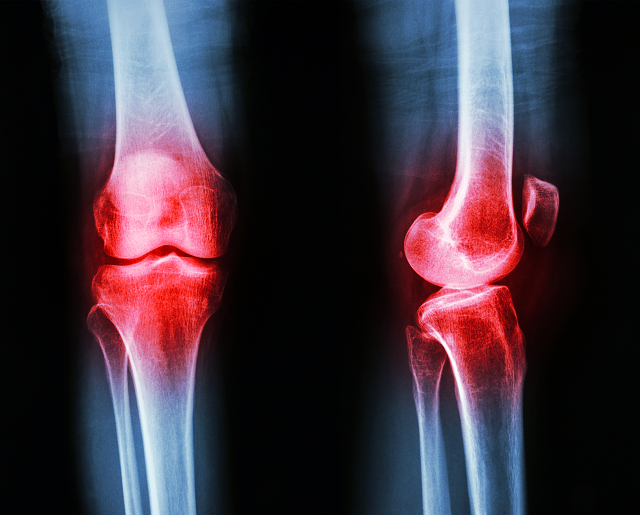

Condromalacia femoropatelar grado 4: causas, síntomas y tratamiento

La condromalacia femoropatelar es una lesión en la rodilla que se produce cuando el cartílago que recubre la superficie de la rótula y el fémur se desgasta. Esta lesión puede ser de diferentes grados, siendo el grado 4 el más avanzado y grave. En este grado, el cartílago se ha desgastado por completo, lo que provoca dolor intenso y limitación en la movilidad de la rodilla. En este artículo, hablaremos sobre las causas, síntomas y tratamiento de la condromalacia femoropatelar grado 4.

La condromalacia grado 4 es una lesión de rodilla que se produce cuando el cartílago de la articulación se desgasta por completo. Esta lesión es muy dolorosa y requiere atención médica inmediata.

Los síntomas de la condromalacia grado 4 incluyen dolor intenso en la rodilla, hinchazón y dificultad para mover la articulación. Si no se trata adecuadamente, esta lesión puede causar daño permanente en la rodilla y limitar la movilidad del paciente.